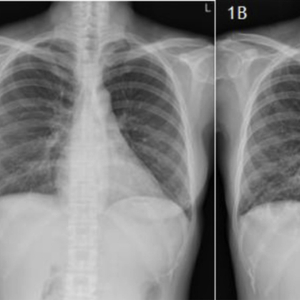

2008年,胸部X线片未见明显异常(图1A)。

图1 A、B、C分别为2008、2015及2016年胸部X线对比

胸片示:除了左下叶实变外,双侧弥漫性线状和网状浸润影,散在细小的囊性病变(图1B)。

2016年1月,复查胸片显示左肺下叶实变明显消退,但双侧肺实质内持续存在囊性病变和网状浸润(图1C)。